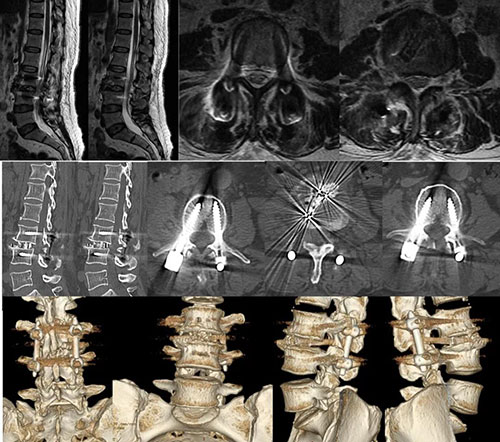

经检查,患者腰3椎体后滑脱,腰3/4节段明显不稳,腰椎CT和MRI检查显示L3/4椎管侧隐窝狭窄,右侧为重。以往此类合并腰椎不稳、腰椎滑脱需行腰椎融合手术的患者,需要经开放切口或管道撑开系统,剥离或劈开椎旁肌,才能完成神经减压、融合器置入、植骨融合等操作。

在助手副主任医师李涛、张稳博士辅助下,蒋振松主任医师成功为患者实施椎间孔镜下腰椎融合手术,这也是山东省立医院首例椎间孔镜下腰椎融合手术。手术出血量约50ml,不用放置引流管。患者术后腰痛及下肢疼痛、麻木症状完全缓解,复查X光片显示滑脱完全复位,内固定物位置良好。复查CT和MRI显示侧隐窝狭窄解除,恢复正常椎管容积。患者术后3天CRP、血沉即恢复正常,佩戴腰围下地活动,随即出院。患者及家属对手术效果非常满意。

术后MRI、CT